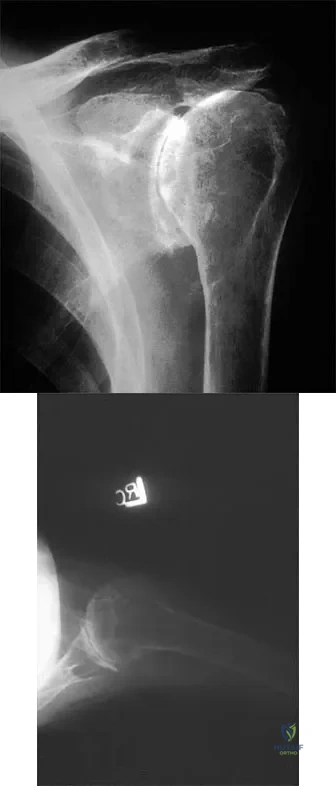

Figure 37 shows the radiograph of a 23-year-old football player who sustained a blow to the anterior aspect of his shoulder. Examination reveals pain and limited rotation. He is unable to flex the arm above the shoulder. Management should include which of the following studies?

Correct Answer: Axillary radiograph

The patient has a posterior dislocation. The radiograph reveals marked internal rotation, but fails to show whether the humeral head is posteriorly displaced. Therefore, an axillary radiograph should be obtained to help confirm the diagnosis. Transverse view CT or MRI scans also may be useful. The other studies will not help confirm the diagnosis. In addition to a direct posterior blow, a shoulder dislocation may be caused by a seizure disorder or electrocution. Bloom MH, Obata WG: Diagnosis of posterior dislocation of the shoulder with the use of Velpeau axillary and angle-up roentgenographic views. J Bone Joint Surg Am 1967;49:943-949.